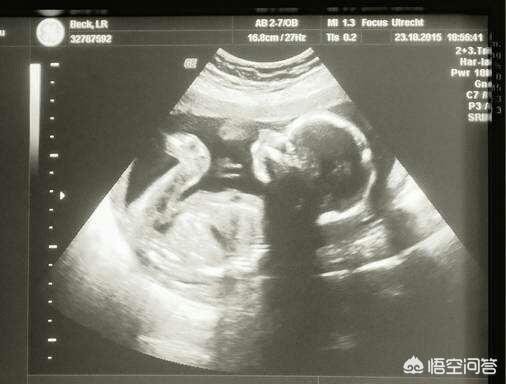

怀孕37周,胎儿偏小两周,其实也算是正常的现象,一般准妈妈用末次月经计算的孕周和B超检查计算的孕周相差在两周以内都是正常的现象。

孕37周,胎儿偏小两周是怎么回事

孕37周胎儿偏小两周有可能的原因主要有以下几点:

1. B超测量误差:由于羊水以及胎儿体位的原因,B超测量胎儿大小预估孕周难免存在误差。

2. 准妈妈末次月经推算不准确:有可能是准妈妈忘记了末次月经的具体时间,也有可能是准妈妈的经期较长。

另外,还有就是因为各种因素的影响(比如遗传、孕期营养等等),每个胎儿的发育情况都是不一样的。其实只要产检正常,准妈妈就不用过于担心。